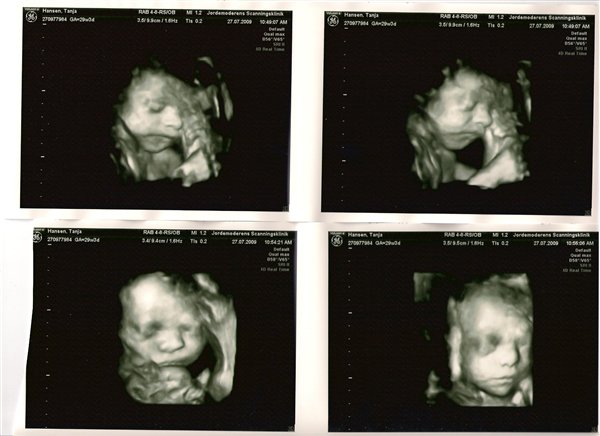

Jeg har lige været til en 3D/4D scanning (27+0), hvilket var en kæmpe oplevelse. Jeg venter en dreng på foreløbig 976 gram

Denne tråd er for alle os som har fået foretaget sådan en scanning. Jeg tænkte det kunne være sjovt at smide nogle fotos op af vores bebzere, da de lå i maven. I profil og forfra.

Skriv gerne hvilken uge scanningen er foretaget, samt evt. hvad køn det er